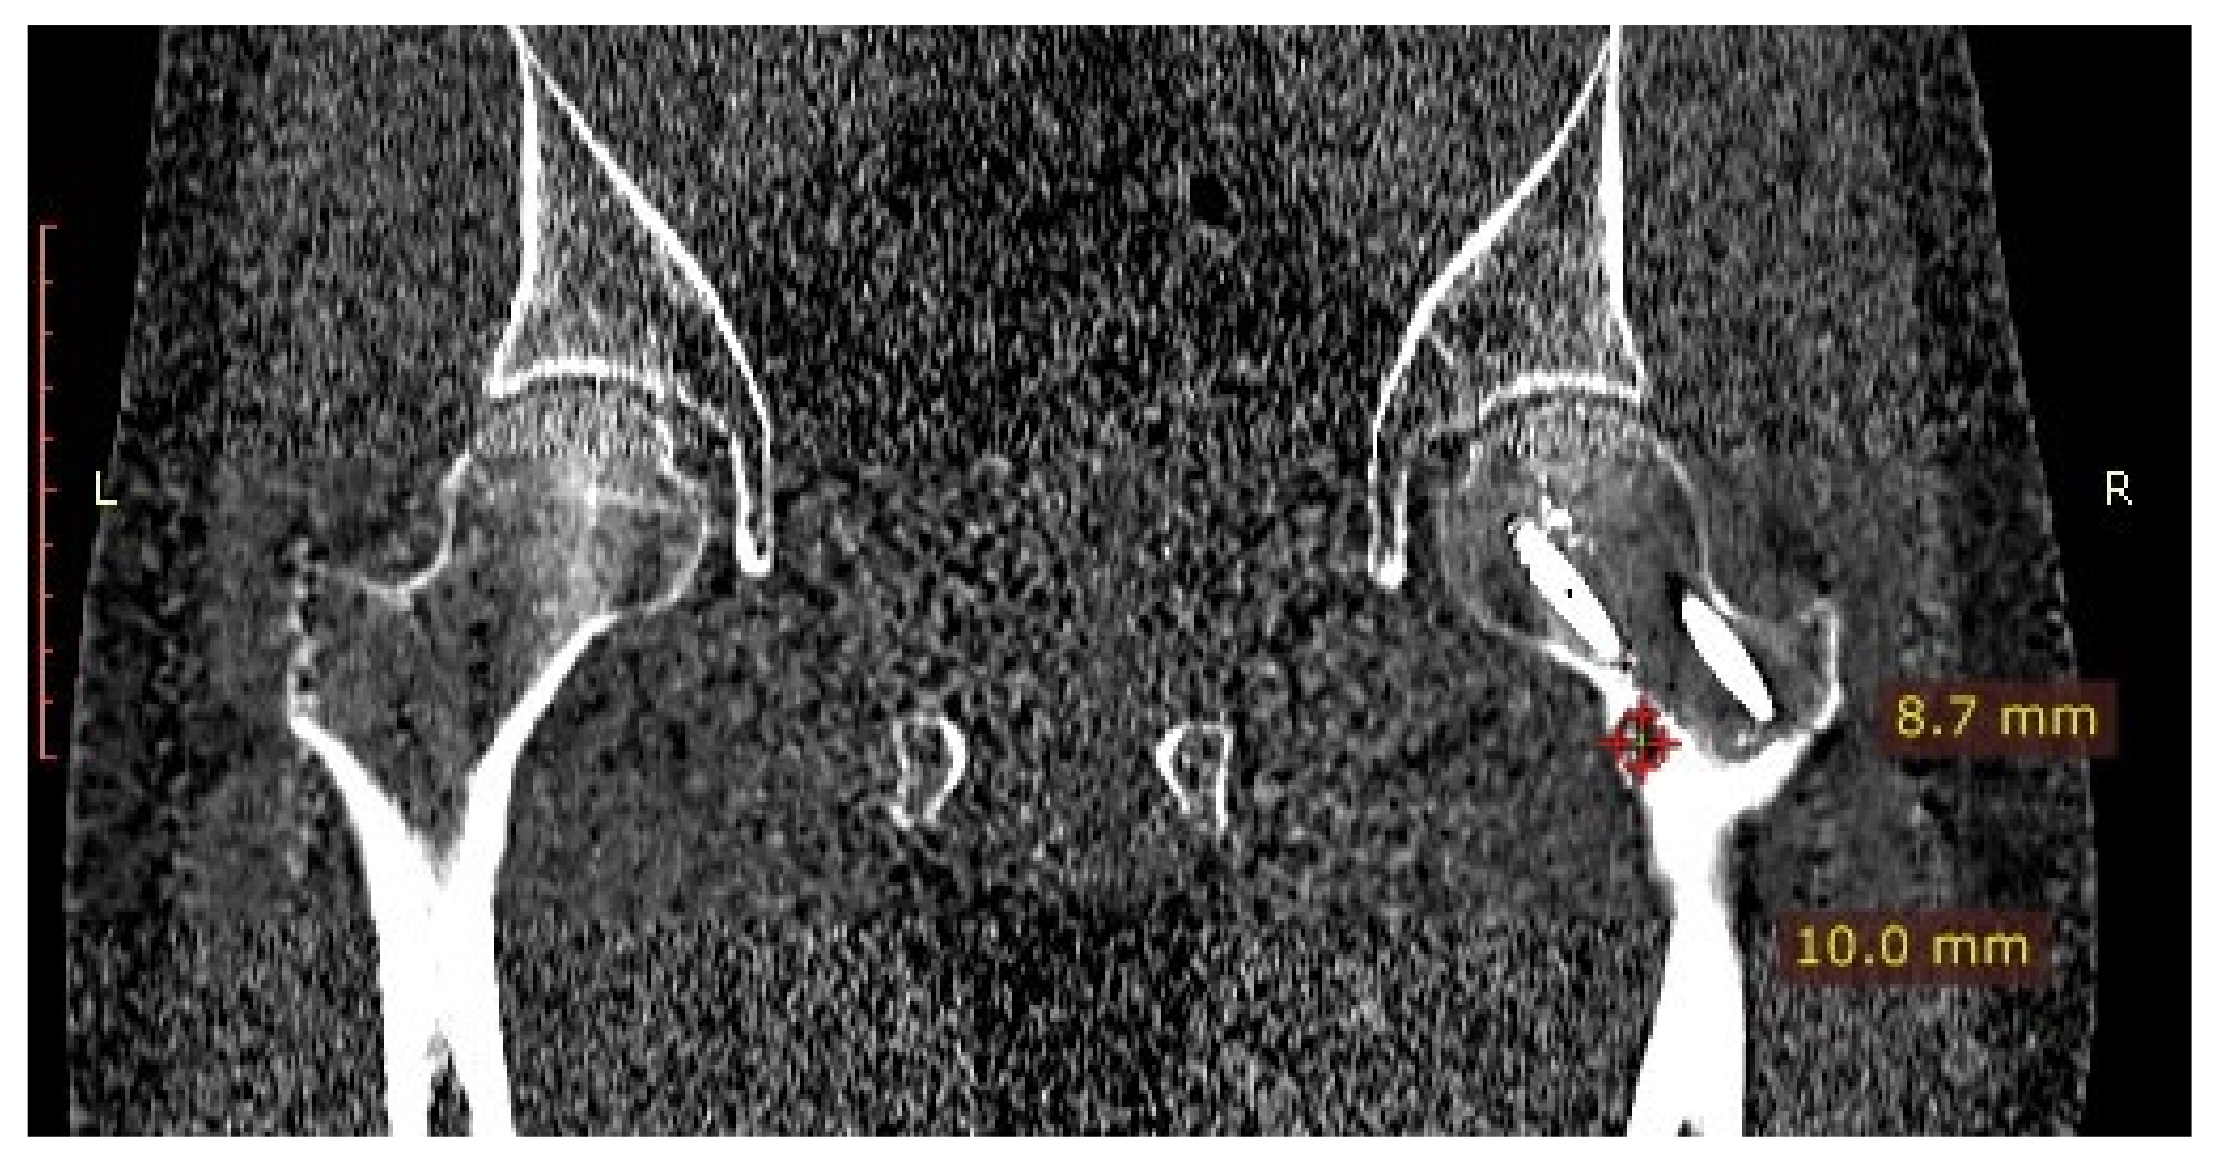

Figure 10.

CT scan of the hip joints showing a focus of OO in the right femoral neck.

A 31-year-old male patient with post-exercise and night pain was seen at an orthopaedic outpatient clinic for diagnosis. The patient underwent a pelvic X-ray and an MRI scan of the right hip joint. The MRI description suggested a suspected fatigue fracture of the right femoral neck (Figure 8). The patient was qualified for surgery. Under general anaesthesia, internal stabilisation was made with three cannulated screws (Figure 9). During the following six months after surgery, the pain did not resolve. During further diagnosis, the patient had a CT scan of the hip joints. The examination revealed a focus of OO of 10 × 9 × 6 mm in the right femoral neck (Figure 10). The patient underwent thermoablation with intraoperative 3D navigation without complications (Figure 11). The VAS score of pain on the day of surgery was 7. Night and postoperative pain resolved completely. The VAS score on examination 3 months after surgery was 0. Cannulated screws were not removed.

Intraoperative photographs during thermoablation with 3D navigation. Cannulated screws were unscrewed for the time of ablation, and reinserted after the procedure.